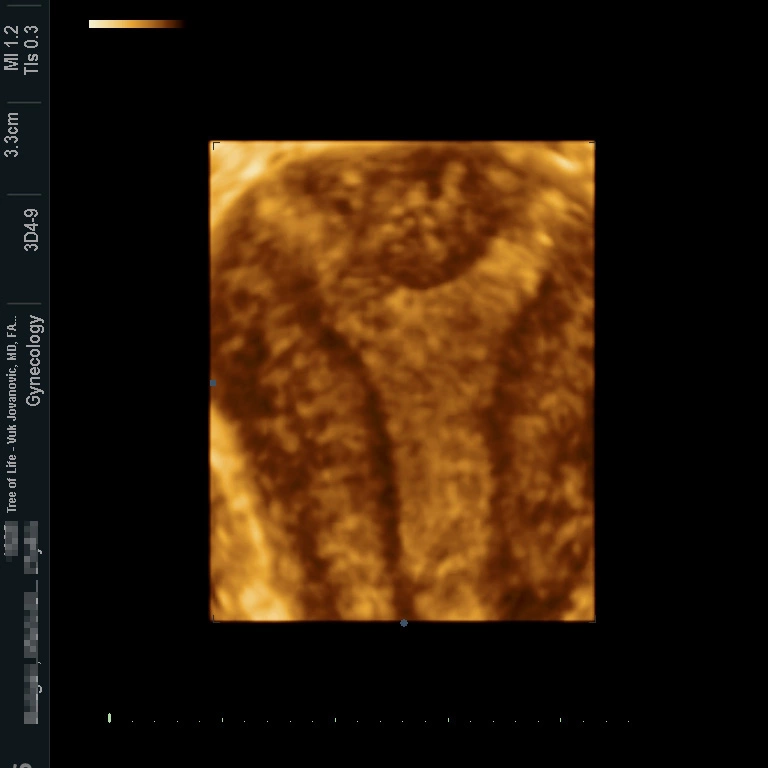

At the Tree of Life Center, we use a 3D vaginal ultrasound to determine the extent of the uterine anomaly and create a 3D picture of the uterine cavity. Our software allows us to rotate the virtual image of the uterus in any dimension so that all issues are clarified. The 3D ultrasound allows for three dimensional reconstruction of the uterine cavity with visualization that is superior to an HSG and can clearly identify the uterine septum. While a good sonographer might recognize a septum on 2D ultrasound, a detailed visualization and image post-processing can only work with a 3D ultrasound device. In comparison, the HSG fills out the cavity with contrast and utilizes low dose radiation. We see a lot of images taken in the wrong plane and the uterine shape can not be clearly seen on some studies. The HSG can not really adjust the plane and it mainly depends how your uterus lies in the abdomen. The 3D sonography can rotate the image using computer post-processing of the ultrasound data into the desired plane. Therefore, regardless how your uterus is positioned during the ultrasound acquisition, the correct plane can be adjusted. In addition to finding the right plane, the ultrasound will visualize the myometrium (the muscular layer that surrounds the cavity). This again allows us to see the uterine cavity and the entire uterus around it! The 3D sonography is therefore only comparable to a uterine MRI. However the MRI is very expensive and patients need to inject Gadolinium as a contrast medium and stay in the tube for a prolonged period of time. Some patients need to abort the MRI due to not tolerating the confined space or the IV contrast medium.We have included an image No.1 of a patient who was diagnosed with a uterine septum at our Tree of Life Center Los Angeles fertility clinic. We went ahead and did a surgical resection of the uterine septum and the image No.2 after surgery is included. A tiny residual where the septum was can still be seen, but the large indentation and Y-form cavity has been surgically corrected.